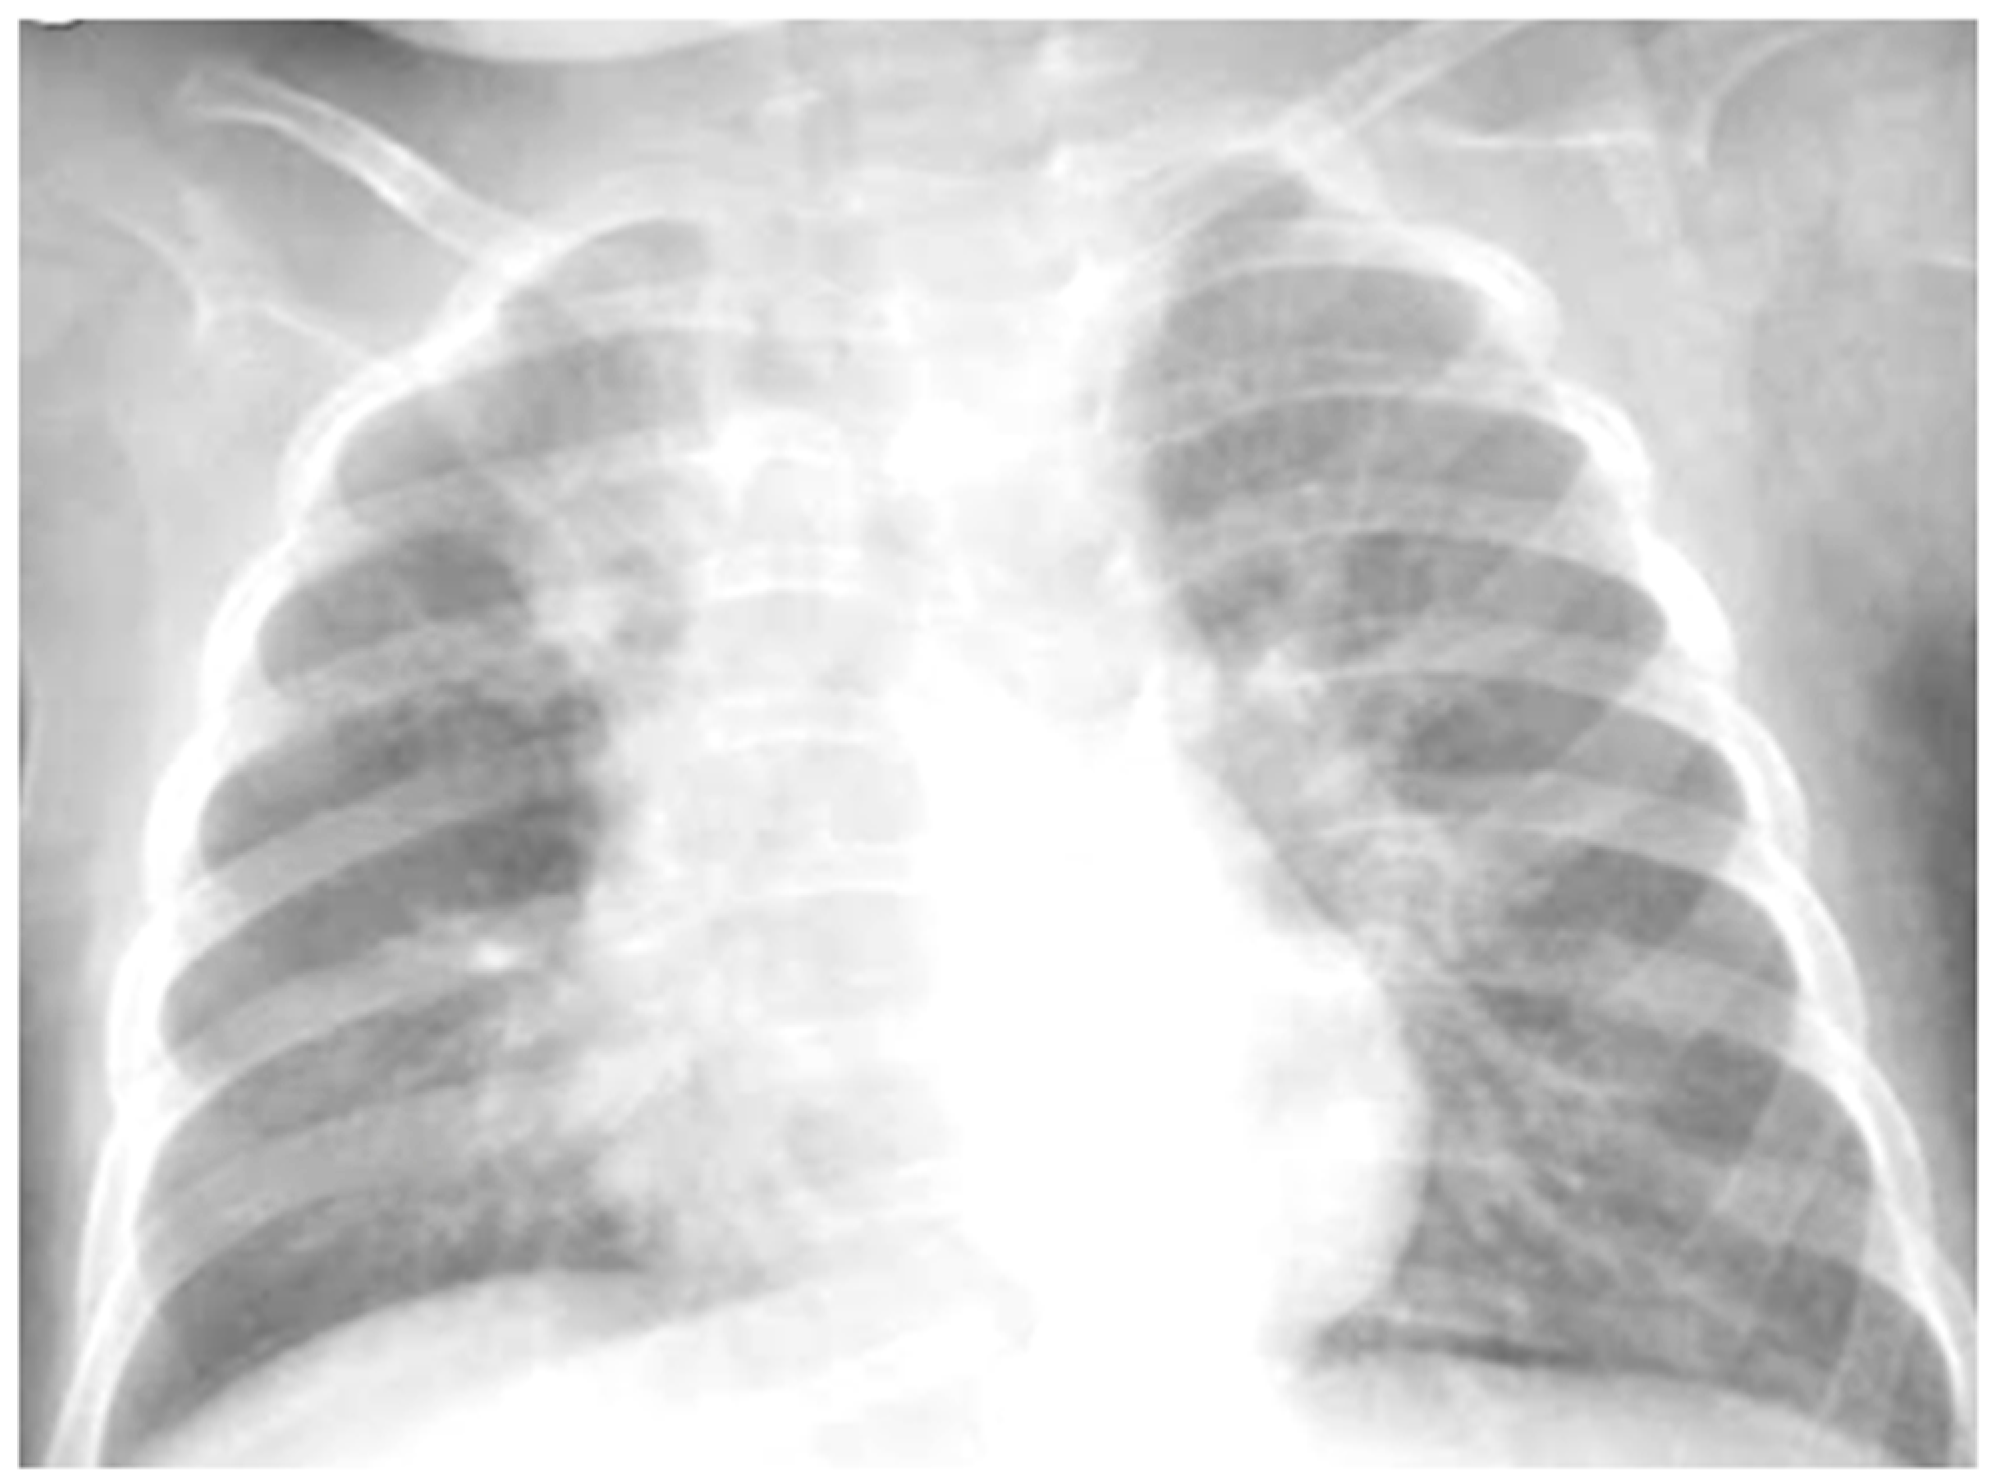

She was moderately dyspneic, in good general condition, and with stable vital signs. She had a slight rise in the indexes of inflammation. At the PED, a chest X-ray was performed to exclude an infectious picture in consideration of the auscultator finding of reduced air penetration in the right hemi thorax. The radiographic picture (Figure 4) was interpreted as an inflammatory type consolidation. Therefore, therapy for acute asthma attack and antibiotic therapy was set up, and she was hospitalized in the pediatric ward. Here, at the same time as the clinical evaluation, we performed LUS, which showed the presence of a picture of SIS, and several areas of lung atelectasis, one of which involved the middle lobe—localized in the right anterior mid-apical area (paracardiac) (Figure 5). The LUS picture was highly positive, but excluded the presence of inflammatory/infectious consolidations. On the basis of these data, the antibiotic therapy was therefore suspended, high flow oxygen therapy was set in consideration of the presence of atelectasis areas, and therapy of the moderate–severe acute attack was continued with subsequent suspension of respiratory support after about a week of therapy. Furthermore, the microbiological investigations of the airways were positive for adenovirus. An adequate preventive therapy was set up [1,2,3]. LUS follow-up showed a complete resolution of the areas of atelectasis after 2 weeks from the start of preventive therapy, and of the SIS after about 4 weeks from the start of the therapy itself.

Figure 4.

Chest radiography shows, on the right fields in the apical and basal areas, a non-specific area of reduced transparency. It also shows signs of interstitial engagement in the para-hilar position bilaterally.

However, regarding chest X-ray, it does not provide useful information for the design of treatment plans for children with acute asthma [16], as in the vast majority of cases, it is completely negative, and in a minority, it is suggestive of atelectasis and/or thickening of the interstitium: elements that are often confused with a radiographic picture of pneumonia, with subsequent administration of antibiotic therapy not necessary to modify the outcome of acute asthmatic attack [16], just as it happened in the first three of our cases. The studies carried out so far are, in fact, all in agreement that chest X-ray is often not helpful in asthma [16].